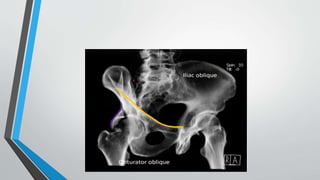

JUDATEVIEW

Types:

I. Obturator oblique

II. Iliac oblique

• Oriented 45 degrees to coronal plane

• Obturator ring is perpendicular (orthogonal) to iliac wing

• Iliac oblique of one hip is obturator oblique of contralateral hip

i.Obturator oblique

• Injured hemipelvis bumped up, toward Xray beam.

• Iliac cross section is small as possible

• Perfectly displays outline of the obturator ring

• Best demonstrates

1)Anterior column 2) Posterior wall